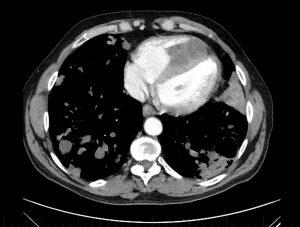

Figure 4

CT pulmonary angiogram: axial view.

There is a dense mass within the RV chamber due to a hydatid cyst. There is reduced RV blood filling in diastole due to the space occupying mass. The interventricular septal wall is clearly demarcated and the mass appears to encroach on the septal wall at two points. The RV is enlarged and occupies the apex of the heart. The sternum has been divided in two parts from a previous stenotomy (with incomplete surgical resection of the mass, leading to regrowth). There is a cavitating lesion in the posterior aspect of the left lung.